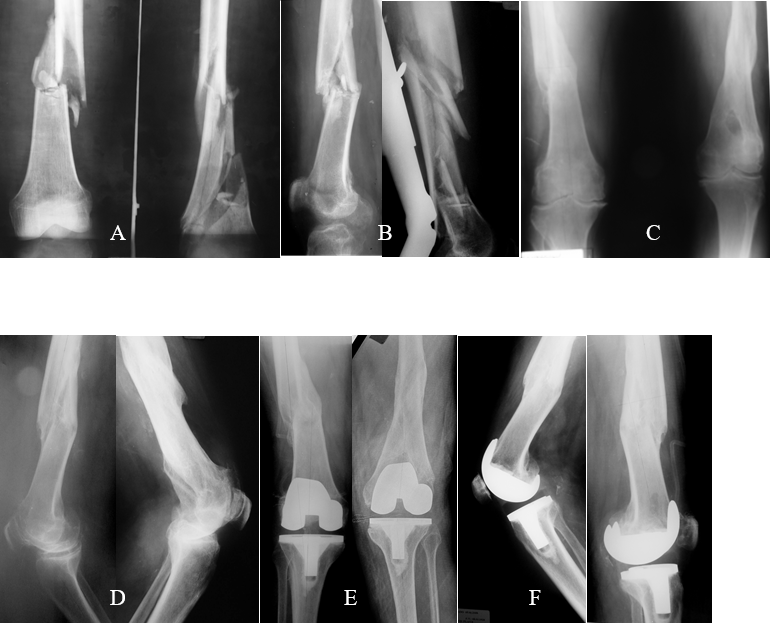

Figura 5 : a, b, c) paciente masculino de 35 años de edad, que sufre de hemimelia peronea del miembro inferior izquierdo. Presenta gonartrosis grave homolateral, osteosíntesis femoral homolateral y deformidad tibial de 20° en varo y 28° de antecurvatum; d, e) gonartrosis grave, subluxación posterior de la tibia y patela baja. f, g) A-P y perfil de la ATR. Fue necesario realizar una osteotomía de la TAT.